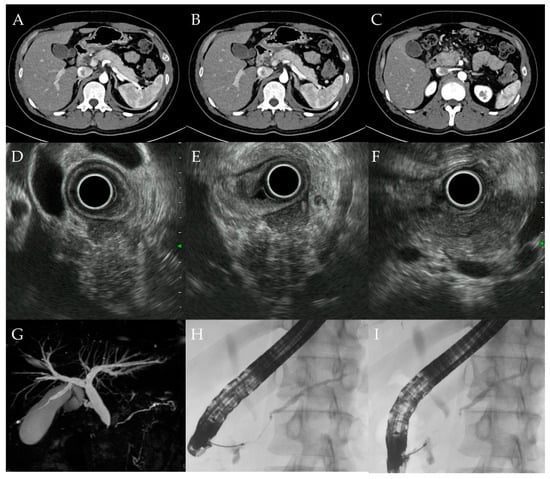

3.4. Case Report (Case 10)